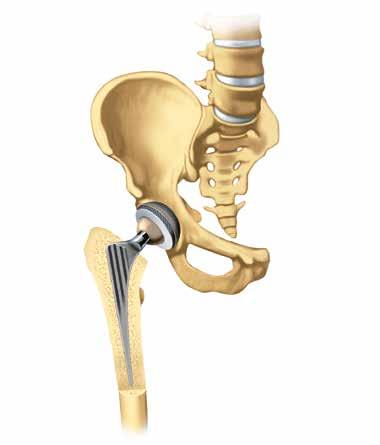

Gelenkersatz

Hat die Arthrose ein Gelenk bereits stark zerstört, kann das Einsetzen einer Prothese helfen, Betroffenen verloren gegangene Lebensqualität wiederzugeben. Schmerzen und Bewegungseinschränkungen können gelindert und oft sogar ganz zum Verschwinden gebracht werden. Selbständigkeit wird wieder möglich.

Der Fachbegriff für ein künst liches Gelenk lautet «Endopro these», abgeleitet von der grie chischen Vorsilbe Endo «innen». Endoprothese bedeutet also, dass ein künstliches Ersatzteil ins Körperinnere eingesetzt wird und dort für lange Zeit verbleibt.

Die am häufigsten eingesetzten Endoprothesen sind die der Hüft-, Knie- und Schultergelenke.

In vielen Spitälern gehören sie inzwischen zu den Standardoperationen. Ein künstliches Gelenk besteht aus mehreren Teilen:

In der Regel ist die Prothese aus Cobalt-Chrom oder Titanlegierungen, die Gleitpartner sind aus sehr harten Polyethylen-

Kunst stoffen und Keramik gefertigt. Bevor das Implantat eingesetzt wird, muss der geschädigte Gelenkknorpel entfernt werden. Chirurginnen und Chirurgen werden natürlich immer versuchen, nur so wenig Knochen abzutragen wie unbedingt nötig. Bei manchen Gelenken, wie beispielsweise dem Knie, kommen auch Teilprothesen zum Einsatz, wenn nur ein begrenzter Abschnitt des Gelenks zerstört ist.

Beckenknochen

Hüftgelenkpfanne

Oberschenkelhals Hüftkopf Gelenklippe

Oberschenkelknochen